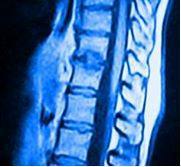

Os Nódulos de Schmorl são pequenas depressões na superfície dos corpos vertebrais, resultado das pressões exercidas pelos discos intervertebrais, o que provoca a herniação e o deslocamento do tecido dos discos intervertebrais para os corpos vertebrais adjacentes.

Os nódulos de Schmorl podem ser diagnosticados por raio-X, mas a melhor forma é por ressonância magnética.